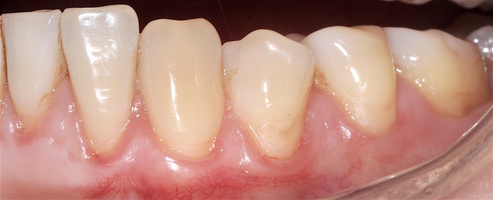

Послеоперационный период после всех операций протекал спокойно, без воспаления и особенностей, реактивный отек соответствовал норме в случае применения аутотрансплантата и ТМО (dura mater).

Реактивность в области применения ТМО и аутотрансплантата была сопоставима и сравнима с травмой мягких тканей при хирургическом вмешательстве. Имеет место реакция в обоих случаях на операцию, но на материал ТМО реакция отсутствует.

Во всех случаях применения аутотрансплантата и ТМО (dura mater) наблюдается сопоставимый положительный клинический результат по всем параметрам оценки рецессий десны (табл. 4). В случае нескольких зубов в области наиболее глубоких рецессий с наименьшими клиническими показателями имеет место сохранение класса рецессии не более первого класса (9 зубов) и глубиной не более 2 мм, 1.6 зуб — 3 мм.

В зарубежной литературе встречается также совокупный показатель эффективности лечения рецессий десны — процент закрытия корня зуба — отношение разница между конечным и исходным значениями глубины рецессии к исходному значению в процентах. Положительный результатом лечения является значение равное или более 80% [4]. Использование только показателя глубины рецессии десны для анализа эффективности лечения без учета остальных показателей (ТКД, ШКД, РРД, ЗДК) не дает полной картины результата и может быть применимо только в совокупности с другими показателями (рис. 6а-й).

Так в нашем случае процент закрытия корня зуба наблюдается больше 80% у 13 зубов. Менее 80% — у 11 зубов. Это связано с сохранением класса рецессии после лечения в области зубов с наибольшим классом рецессии и наибольшим показателем глубины рецессии. При этом средний показатель всех 24-х оперированных зубов — 83,1%. При этом среднее значение процента закрытия корня зуба для зубов с положительным результатом (более 80%) составляет 96,65%. Среднее значение для результатов менее 80% — 54,73, что связано с изменением глубины рецессий с 6 мм до 3 мм, с 4 мм до 2 мм и с 2 до 1 мм. При этом для аутотрансплантата и для ТМО результаты сопоставимы.